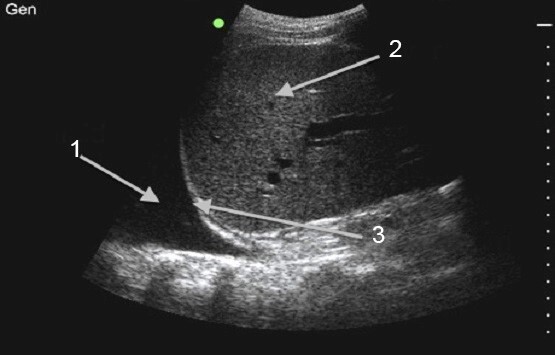

Thoracentesis Procedure Image

Fluid (Effusion)

Liver

Diaphragm